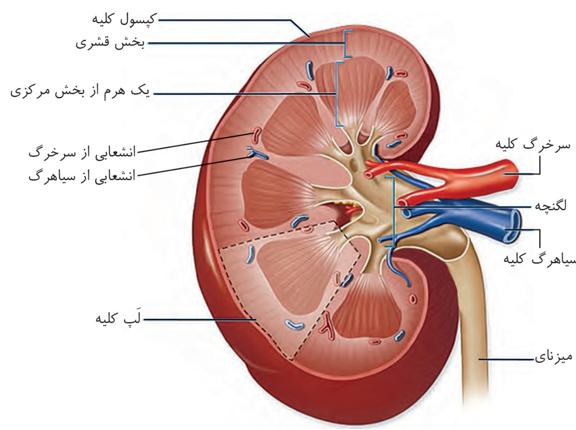

در برش طولی کلیه، سه بخش مشخص دیده میشود که از بیرون به درون عبارتاند از بخش قشری، بخش مرکزی و لگنچه.

در بخش مرکزی، تعدادی ساختار هرمی شکل دیده میشود که هرمهای کلیه نام دارند. قاعده هرمها به سمت بخش قشری و راس آنها به سمت لگنچه است. هر هرم و ناحیه قشری مربوط به آن را، یک لَپ کلیه مینامند.

لگنچه، ساختاری شبیه به قیف دارد. ادرار تولید شده، به آن وارد و به میزنای هدایت میشود تا کلیه را ترک کند.

بخش قشری:

۱-خارجیترین بخش هر کلیه است.

۲-بخش کمی از حجم هر کلیه را در بر میگیرد.

۳-این بخش از خارج با کپسول کلیه در تماس است.

۴-در بخش قشری انشعاباتی از سرخرگ و سیاهرگ کلیه مشاهده میشود.

بخش مرکزی:

۱-قطورترین بخش هر کلیه است.

۲-راس هر هرم به یک مجرا ختم میشود که از طریق آن ادرار تولید شده توسط نفرونها به لگنچه منتقل میشود.

۳-در هر لپ کلیه در دو سمت هر هرم، انشعاباتی از بخش قشری وجود دارد.

۴-هر هرم در محل اتصال به لگنچه رنگ روشنتری دارد.

لگنچه:

۱-داخلیترین بخش هر کلیه در برش طولیست.

۲-ساختاری شبیه به قیف دارد.

۳-در این بخش کلیه تغییری در ترکیب شیمیایی مایع وارد شده به آن صورت نمیگیرد.

کوچکترین هرم کلیه بالاتر از سرخرگ کلیه قرار دارد.

انشعاباتی از سرخرگ کلیه میتواند در پشت لگنچه حضور پیدا کند.

بخش قشری کلیه از بخش مرکزی تیرهتر است.

در ناف کلیه چربی وجود دارد.